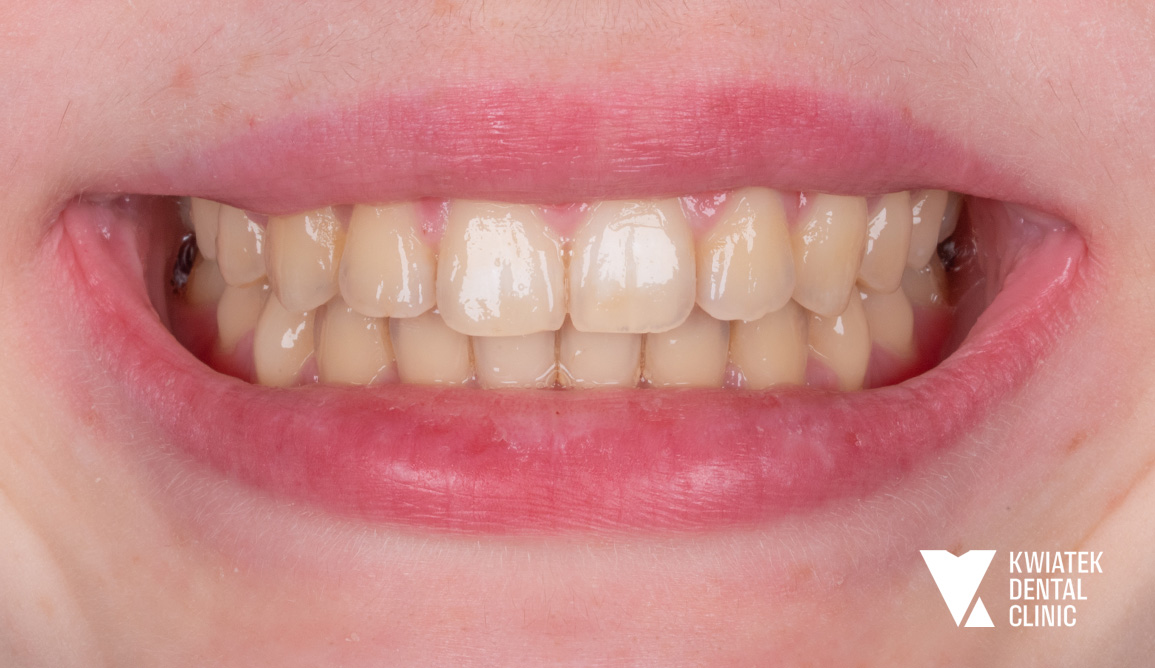

Luksus dyskretnej ortodoncji oparty na zaawansowanej technologii nakładkowej

Pacjentka zgłosiła się do kliniki z potrzebą kompleksowej poprawy zarówno funkcji zgryzu, jak i estetyki uśmiechu. W badaniu stwierdzono zgryz krzyżowy, stłoczenia zębów oraz liczne problemy wymagające leczenia zachowawczego i protetycznego, co wymagało wieloetapowego, interdyscyplinarnego podejścia. Terapię poprzedziło staranne przygotowanie jamy ustnej obejmujące ekstrakcję zębów mądrości, profesjonalną higienizację oraz odbudowę osłabionych struktur. Następnie wdrożono zaawansowane leczenie ortodontyczne z wykorzystaniem nowoczesnego systemu nakładkowego. Rezultatem jest harmonijny, stabilny zgryz, idealnie ukształtowane łuki zębowe oraz wyraźnie odmłodzony, jasny uśmiech, podkreślony profesjonalnym wybielaniem.